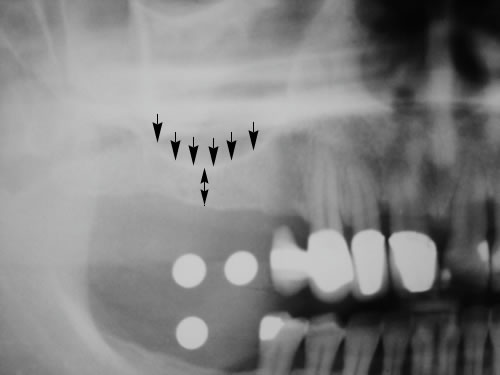

Die zahnärztliche Untersuchung umfasst die Beurteilung der gesamten Mundhöhle, der Schleimhaut, der Zähne und der Kieferknochen. Wenn eine Einpflanzung in Erwägung gezogen wird, muss eine Röntgenmessaufnahme angefertigt werden. Dazu wird nach einem Kieferabdruck eine Planungsschablone hergestellt, in die Metallkörper (Kugeln oder Stifte) an den Stellen eingearbeitet sind, an denen eine Implantation geplant ist (Abb. 5.1, 5.2). Diese Platte wird in den Mund des Patienten eingesetzt und die Röntgenaufnahme angefertigt (Abb. 5.3, 5.4).

Abb. 5.2: Planungsschablone mit genormten Hülsen an den geplanten Implantationsstellen.

Abb. 5.3: Eingesetzte Planungsschablone vor dem Röntgenbild.

Abb. 5.4: Kugelmessaufnahme zur Planung der Implantatlängen.

Da die Größe der Metallkörper, die auf der Aufnahme gut sichtbar sind, bekannt ist, kann aus dem Röntgenbild die zur Verfügung stehende Knochenhöhe sehr genau errechnet werden.